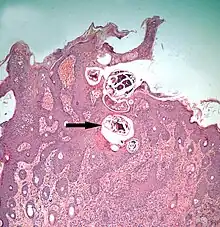

Section through skin infested with Demodex in the hair follicles (arrowed), which are surrounded by infiltration of inflammatory cells

Demodecosis

Demodecosis in cattle caused by Demodex bovis can occur as dense, localized infestations with inflammation of the epidermis in hair follicles.[36] This leads to pustular folliculitis and indurated (thickened) plaques within the skin. On cattle, these localized foci of infestation can become so large as to be clearly visible externally. The value of the hides from cattle infested this way is reduced.[37] Pigs may be similarly affected by infestations with Demodex.[38]